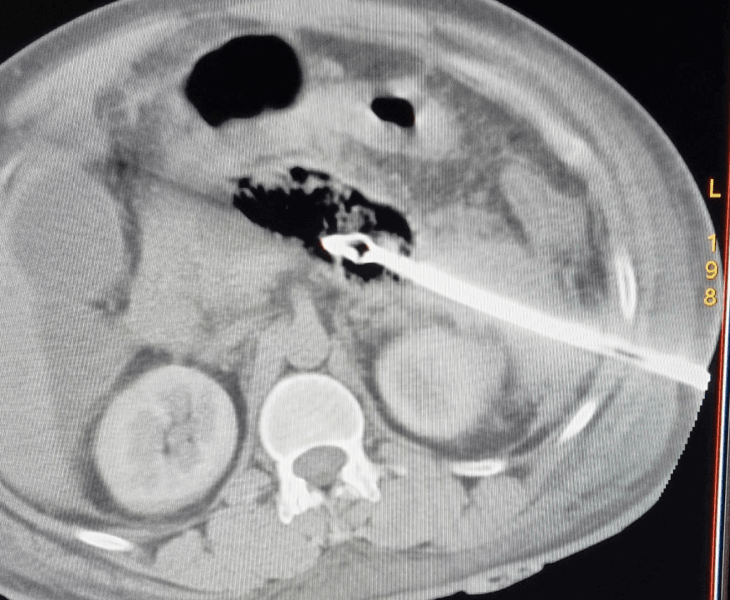

Pancreatic Collection Drainage

CT‑guided catheter drainage to treat infected collections and relieve symptoms.